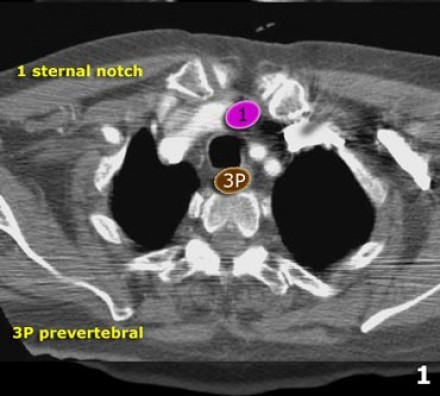

3. Linfonodos Prevasculares e Prevertebrais

Linfonodos estação 3 não estão adjacentes à traqueia como os linfonodos estádio

Eles podem ser:

3A - anteriores aos vasos

3P - posteriormente ao esôfago, prevertebrais

Linfonodos estadio 3 não são acessíveis à mediastinoscopia.

Linfonodos 3P podem ser acessados com ultrassonografia endoscópica.